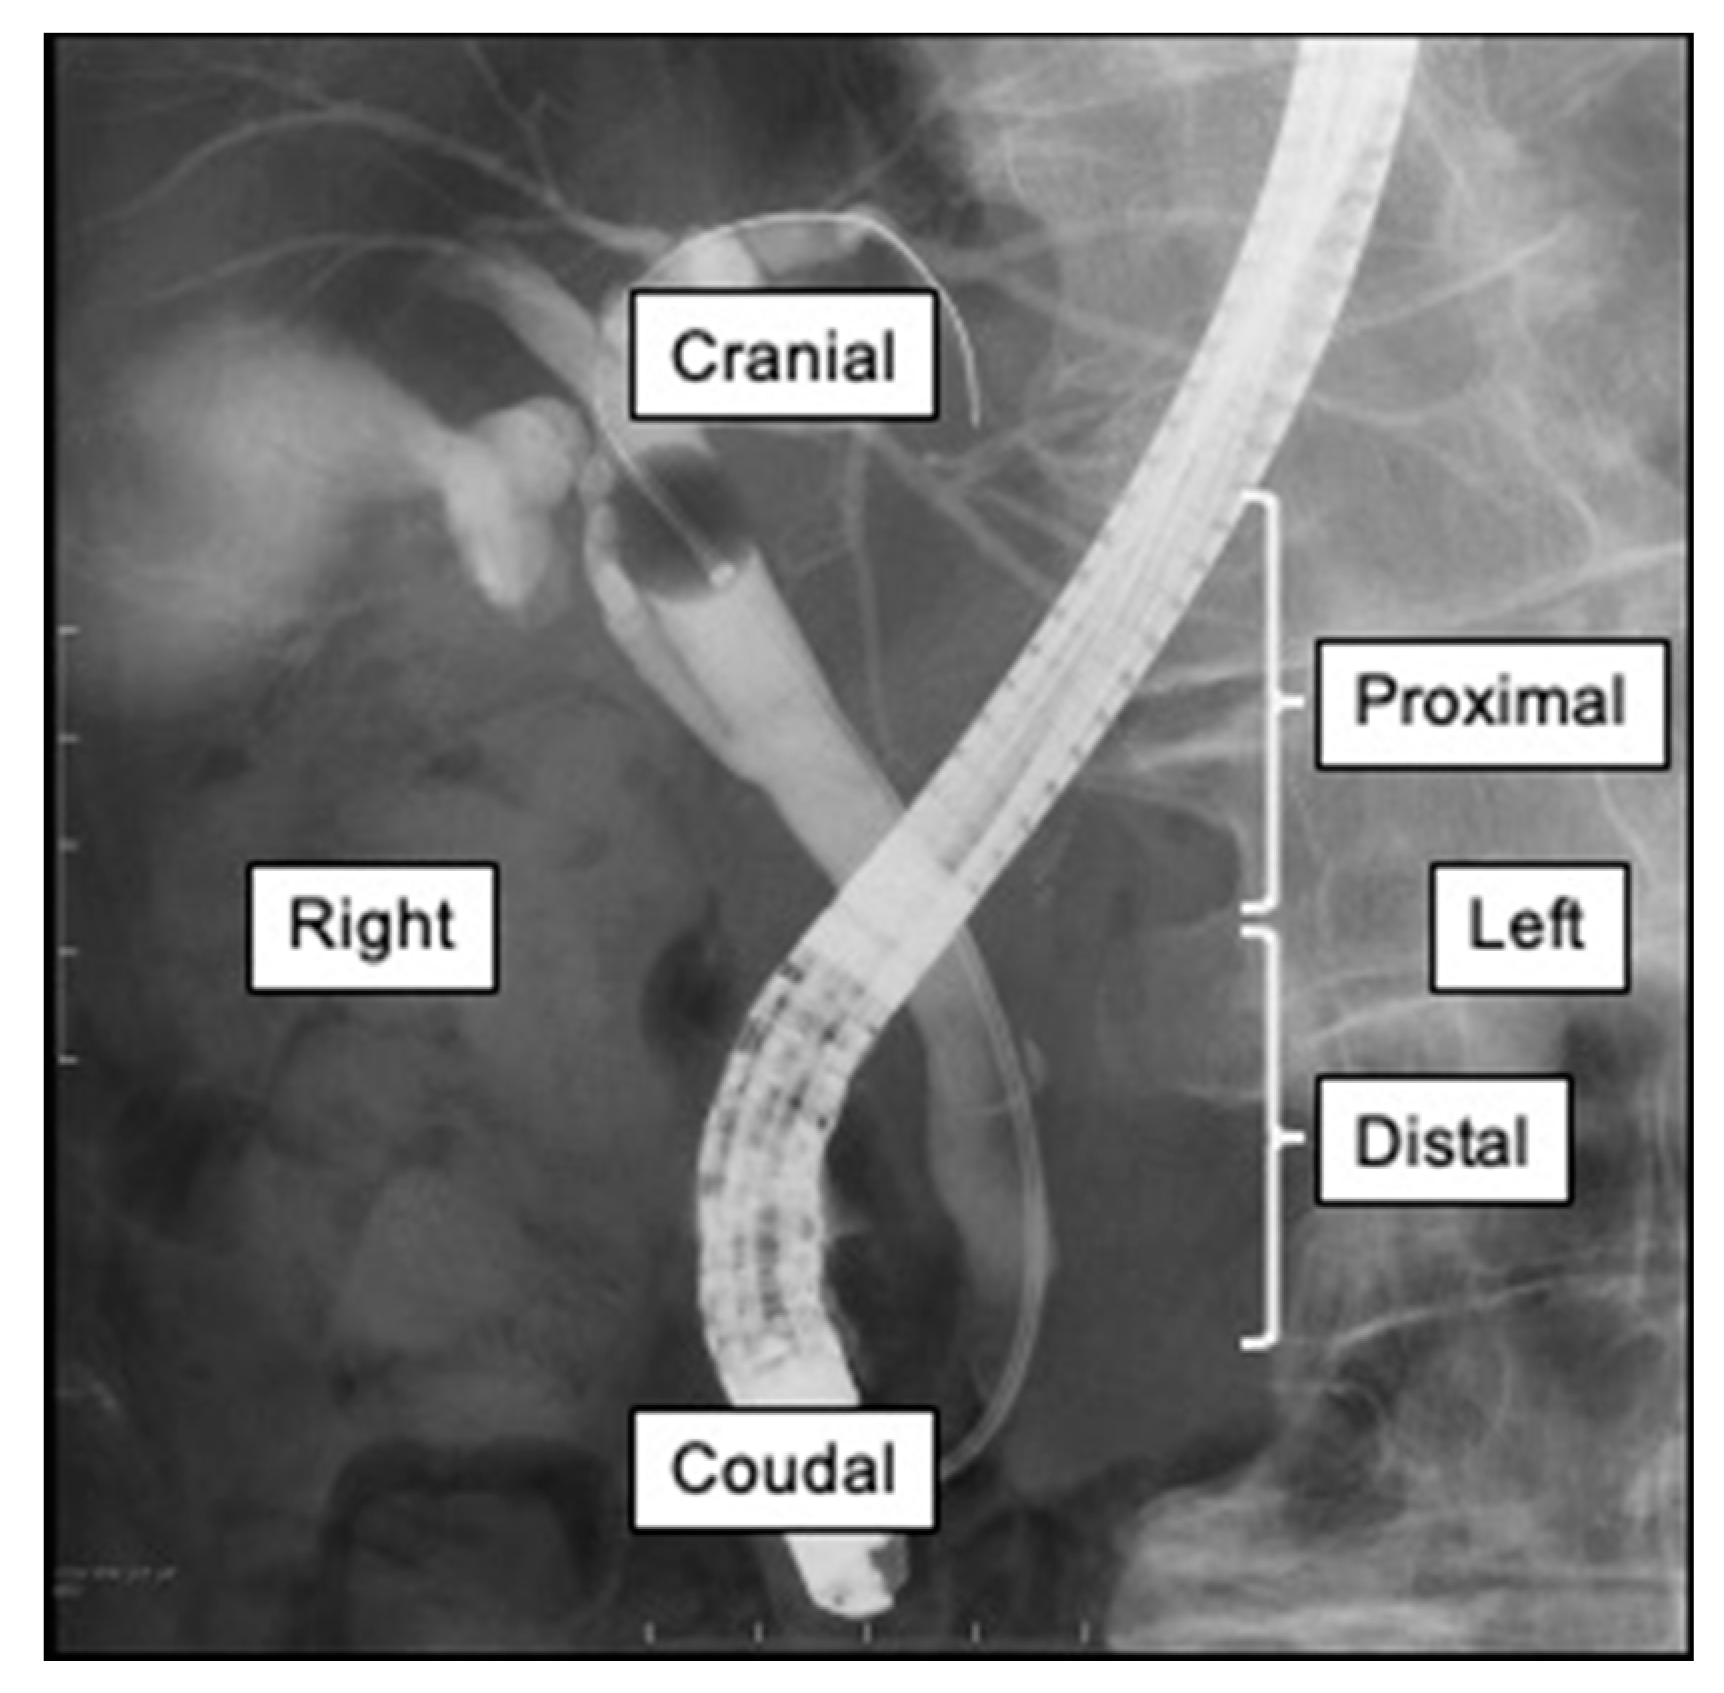

From www.researchgate.net

Occlusion cholangiogram obtained during ERCP showing adequate filling Ercp Without Gallbladder Most commonly, ercps are performed for choledocholithiasis with or without cholangitis, but improvements in technology. Endoscopic retrograde cholangiopancreatography (ercp) is a combined endoscopic and fluoroscopic procedure in which an upper endoscope is led into. Endoscopic retrograde cholangiopancreatography, or ercp, is a procedure to diagnose and treat problems in the liver, gallbladder, bile ducts, and pancreas. Ercp is a technique that. Ercp Without Gallbladder.